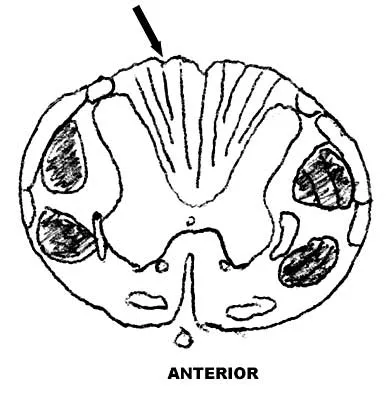

Figure 9 shows a cross-sectional view of the spinal cord at the lower cervical level. Injury to the structure indicated by the black arrow will lead to what neurologic deficit?

The arrow is pointing to the posterior columns of the spinal cord that transmit position sense, vibratory sense, and proprioception. There are no motor tracts in the posterior columns. Bohlman H, Ducker T, Levine A: Spine trauma in adults, in Herkowitz HH (ed): The Spine, ed 4. Philadelphia, PA, WB Saunders, 1992, p 911.